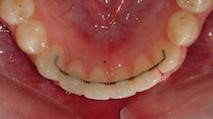

- Fixed retainer – a fixed retainer is a thin wire bonded to the inside/tongue side of the teeth. It is usually used in conjunction with a removable retainer.